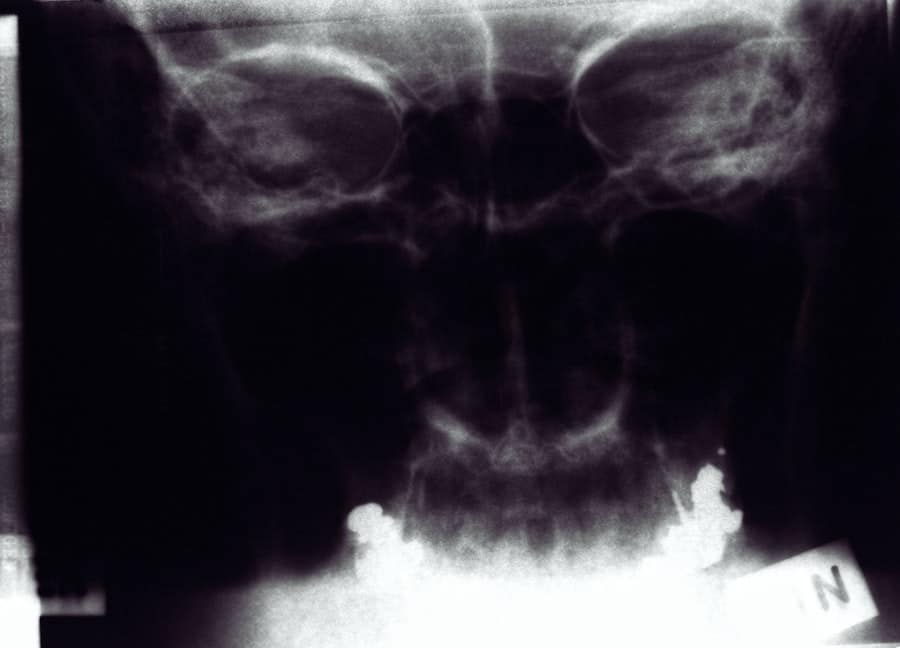

If you’re considering rhinoplasty in Hawthorne, California, it’s essential to understand the costs and find the best plastic surgeon for your needs. While researching, you might also be interested in exploring the combination of sinus surgery and rhinoplasty, which can be a beneficial option for those with both aesthetic and functional concerns. For more information on this topic, you can read a related article on the combination of sinus surgery and rhinoplasty. This article provides insights into how these procedures can be effectively combined to address both cosmetic and medical issues, potentially offering a more comprehensive solution for patients.